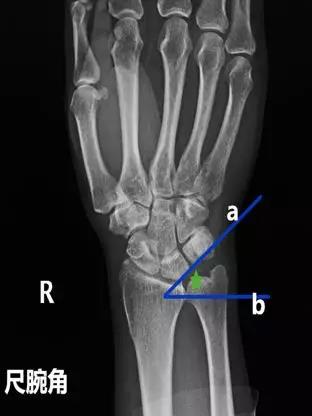

- 尺腕角:在腕关节正位片作月骨和三角骨的外缘切线,并作尺骨远端关节面的切线,此两线所形成的夹角。

- 正常值:21°~51°

- 临床意义:若尺腕角改变,提示腕骨骨折或腕关节脱位。